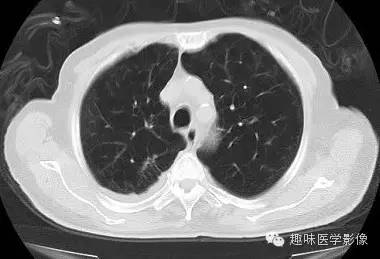

【病例】肺脓肿1例CT影像特点

男,71岁,发热待查。

[影像描述]

双肺多发无壁低密度区,以右肺下叶底部为主。右肺下叶见大片不规则实变阴影伴多发空洞影,实变肺组织内见支气管气象,右肺下叶支气管局部显示不清。纵隔内见淋巴结。右侧胸腔内见积液影,邻近胸膜肥厚。主动脉、冠状动脉钙化。

右肺下叶肺脓肿、肺炎伴胸腔积液,肺气肿、肺大泡。

右胸廓变小,心影右移;右肺下叶多房性空洞,空洞内未见明显液平面,右下肺病变应该是下叶阻塞性肺炎,实变肺组织内见支气管气像,邻近胸膜增厚,并合并胸腔积液,支持肺脓肿。